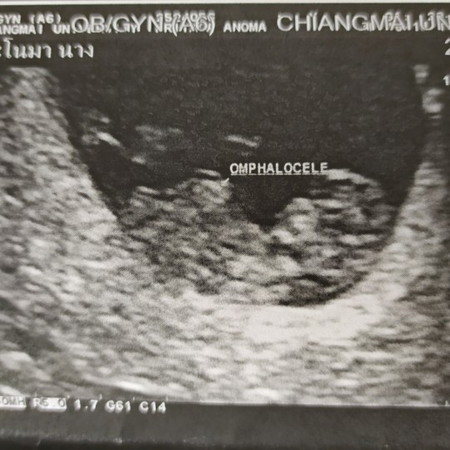

omphalocele

Omphalocele สงสัยมากครับมันคืออะไรเพราะหมอบอกว่าปกติ 10w3d